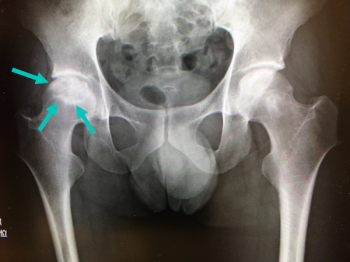

今日、ご紹介するのは、大腿骨の病気 特発性大腿骨頭無腐性壊死についてご紹介していきます。

特発性大腿骨頭無腐性壊死とは

成人の大腿骨頭に明らかな原因がなく、血流の低下により壊死(血が通わなくなって骨組織が死んだ状態)に陥った状態です。

特発性大腿骨頭無腐性壊死の検査・診断・治療

検査・診断

X線、CTスキャン、磁気共鳴画像法(MRI): 骨の変化